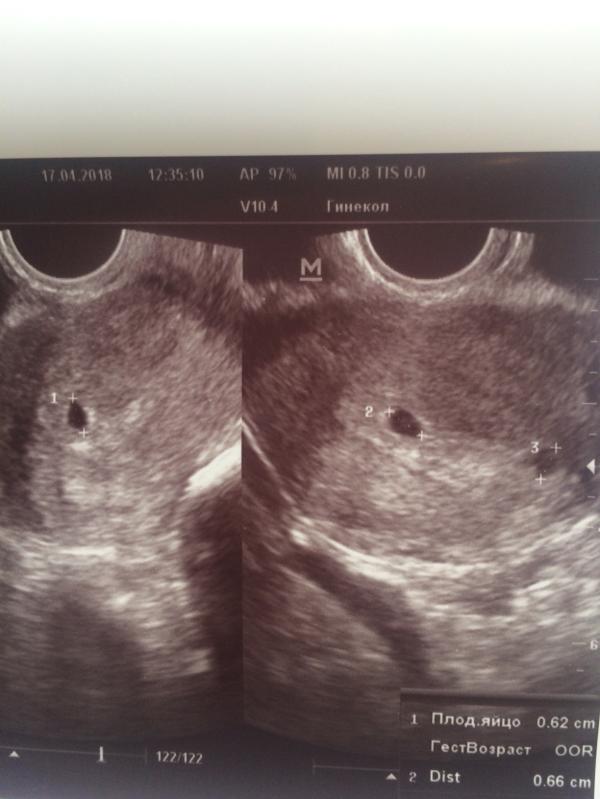

С праздником, девочки! Была сегодня на УЗИ и зла не хватает у меня. Впереди много букв, осторожно. Ну все по порядку, пол года назад я пошла в медок узнать, как там мой шов от кс, мне сказали все норм, но варикоз сильный на матке типо из-за того, что ребёночек был крупный. Я вся расстроенная начиталась в интернете, чем грозит варикоз на матке. Расстроилась, даже записалась у врачу в жк, чтоб там мне выписали, лекарства. Моя врач заболела накануне, записалась к другой, сходила, она написала прост...